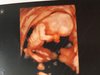

A oto moja kruszynka